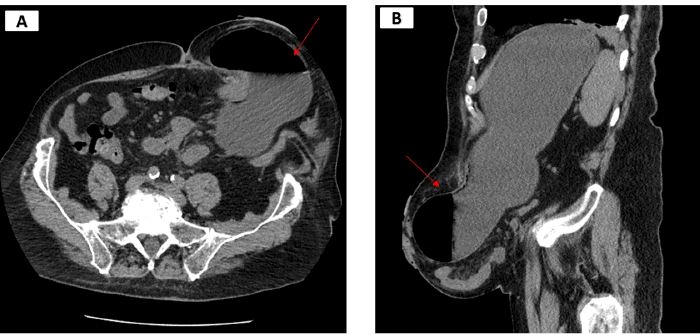

Following multidisciplinary preoperative risk assessment and optimization of his COPD and chronic atrial fibrillation, the patient underwent laparoscopic parastomal hernia repair to prevent future obstructive episodes. Extensive omental and small bowel adhesions surrounding the hernia were lysed, and incarcerated small bowel loops were freed. The size of the defect was measured to be 8 × 8 cm (Figure 2).

Figure 2. Intraoperative View of Parastomal Hernia Defect, Measuring 8 × 8 cm (arrows). Published with Permission

The hernia repair involved a composite mesh (ProceedTM, Ethicon, Somerville, NJ, USA) using a keyhole technique with a 4 cm mesh overlap. The mesh was secured with transfascial sutures and tacks (Figure 3). Gaps between the colostomy and the mesh keyhole were closed with sutures and an omental flap (Figure 3).